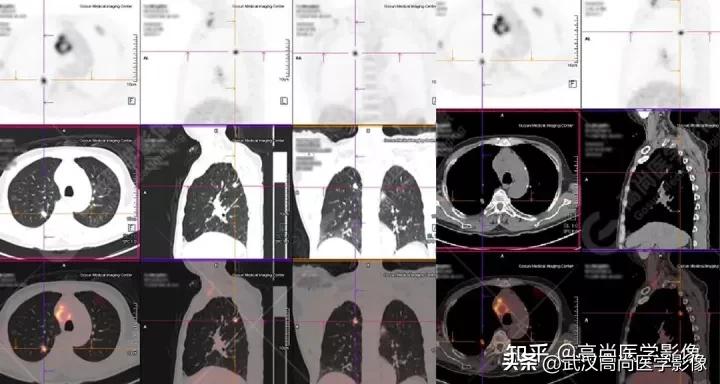

病例三

老年男性63岁,左大腿疼痛1月余,渐加重。

MR检查提示左股骨上段破坏,需排查转移。

左股骨上段溶骨性骨质破坏,SUVmax4.7,怀疑为转移。

全身PET/CT

影像表现:

右肺上叶尖段胸膜下见一实性结节,范围约1.6cm×1.3cm,病灶紧贴邻近胸膜,伴牵拉增厚,FDG高摄取,SUVmax为7.5。

恶性CT征象:

结节边缘不光整,分叶、长短不一的毛刺,邻近胸膜牵拉明显。

右侧胸膜区多发条片状代谢增高影,SUVmax4.7,CT于相应部位胸膜增厚,伴右侧中量胸水。

PET代谢增高,在发现胸膜转移较常规CT扫描有一定的优势。

PET/CT诊断结论

右肺上叶尖段周围型肺癌,累及邻近胸膜;右侧胸膜多发转移,伴中等量胸水;左股骨上段转移。

另外,左肺上叶前段见一团状混杂磨玻璃影,范围约4.3cm×3.3cm,CT值约-662Hu,内部扭曲扩张支气管及血管影穿行,边缘分叶、棘状突起,FDG摄取轻度增高,SUVmax1.3,考虑为多中心起源浸润性肺癌(多原发的肺癌)。